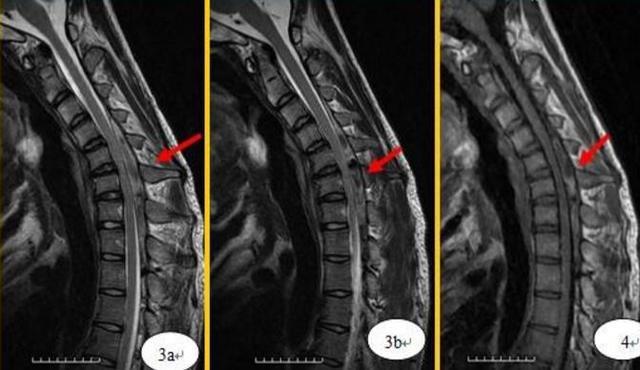

平山病的诊断需要应用特殊的屈颈位-磁共振(mri)以及规范,全面的肌电

答案:平山病(hirayama disease,hd).